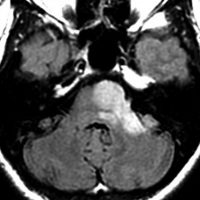

軽度の左下肢の麻痺で発症した50代の患者さんです。一見,かつてのグリオマトーシス gliomatosis あるいは diffuse hemispheric glioma WHO grade 4 のように見える非常に広範囲な病変です。しかし,病理診断は 星細胞腫 IDH mutant WHO grade 2でした。

放射線治療によく反応し,片麻痺は消失して,画像上の腫瘍高信号もほぼ消失しています。